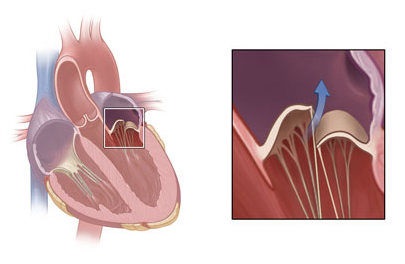

Itt egy tipikus kép egy négykamrás szakaszról, amely szerint az oroszországi echokardiográfusok többsége egyértelműen előidézi a prolapsus MK-t:

Ha a bal szívét vázolja, az orosz doktor-echokardiográfus szokásos akciói a következők:

Tartott egy egyenes vonal a bázis a szélén a elülső betegtájékoztató a mitrális billentyű (PSMK), majd a mért milliméterben elhajlást központ és abban következtetést a jelenléte a beteg elülső betegtájékoztatót előesés MK és annak mértékét.

Ez szerint a legtöbb ehokardiografistov Oroszország szükséges és elégséges a termelés süllyedés diagnózis egy (csúcsi) helyzetben a szelep néz ki, mint egy álla Peter Griffin a híres rajzfilm:

Süllyedés, vagy megereszkedett, az egyik vagy mindkét mitrális szisztolés fázis alatt tartják igaz csak akkor, ha be van jegyezve két echokardiográfiás helyzetben :. Apical négy kamra és parasternalis a hosszanti tengelye mentén a bal kamra „End quote.

Itt van a kutya eltemetve, kedves kollégák, echokardiográfusok. A parasternal helyzetben az úgynevezett "prolapsusok" 99% -a azonnal levágódik.

Gyakran láttál ilyen képet egy parasternal helyzetben? Nem.

Több kép normát és prolapsust tartalmaz. A kép nagyítása egérkattintással. Piros aláhúzta a szelepek szimbólumát és a prolapszust, a sárga nyilak a vér áramlását mutatják a szisztolába:

Néhány világosabban értelmezett illusztráció.

A bal oldalon - Peter Griffin másik fordított üdvözlete a norma ábrázolásában:

Itt látható a mitrális szelep működésének ciklusa (nyitott - zárt) - ismét a szelep szélén lévő probléma: